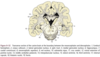

Detail which embryological structures form the different portions of the brain

MRI ANATOMY QUIZ! CAN YOU NAIL IT??